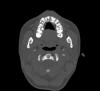

persona Опубликовано 12 октября, 2008 Автор Поделиться Опубликовано 12 октября, 2008 (изменено) Кроме того, проходил КТ. Выкладываю несколько срезов в области клыка. Изменено 12 октября, 2008 пользователем persona Ссылка на комментарий